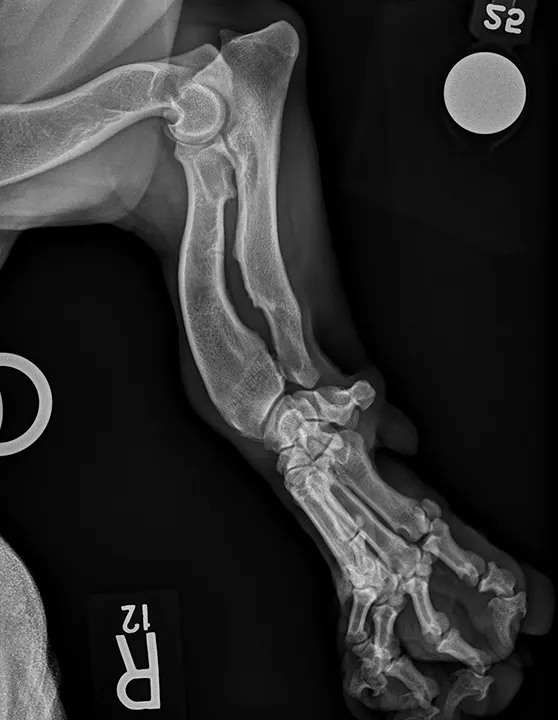

Chondrodystrophic musculoskeletal variations on radiographs are generally based on the difficulty of obtaining straight lateral and craniocaudal radiographs of the thoracic limbs (Figure 6) in chondrodystrophic dogs, whereas large-breed musculoskeletal variations on radiographs are generally based on the difficulty of obtaining straight lateral radiographs of the stifles and tarsi in large-breed dogs.

Positioning chondrodystrophic dogs for musculoskeletal radiographs can be challenging because of their curved humerus, radius, and ulna. It is generally easier to position the thoracic limbs of large-breed dogs as compared with chondrodystrophic dogs, but the pelvic limbs (primarily the tarsus and stifle) may appear oblique due to the large thigh musculature on lateral projections and the inability to completely extend the coxofemoral joints. Use of pads or passive restraint (eg, ropes, tape) and/or tilting the radiographic tube can help optimize the radiographic image. Literature focused on positioning and minimizing the difficulty in interpreting normal radiographs can be found in Suggested Reading.